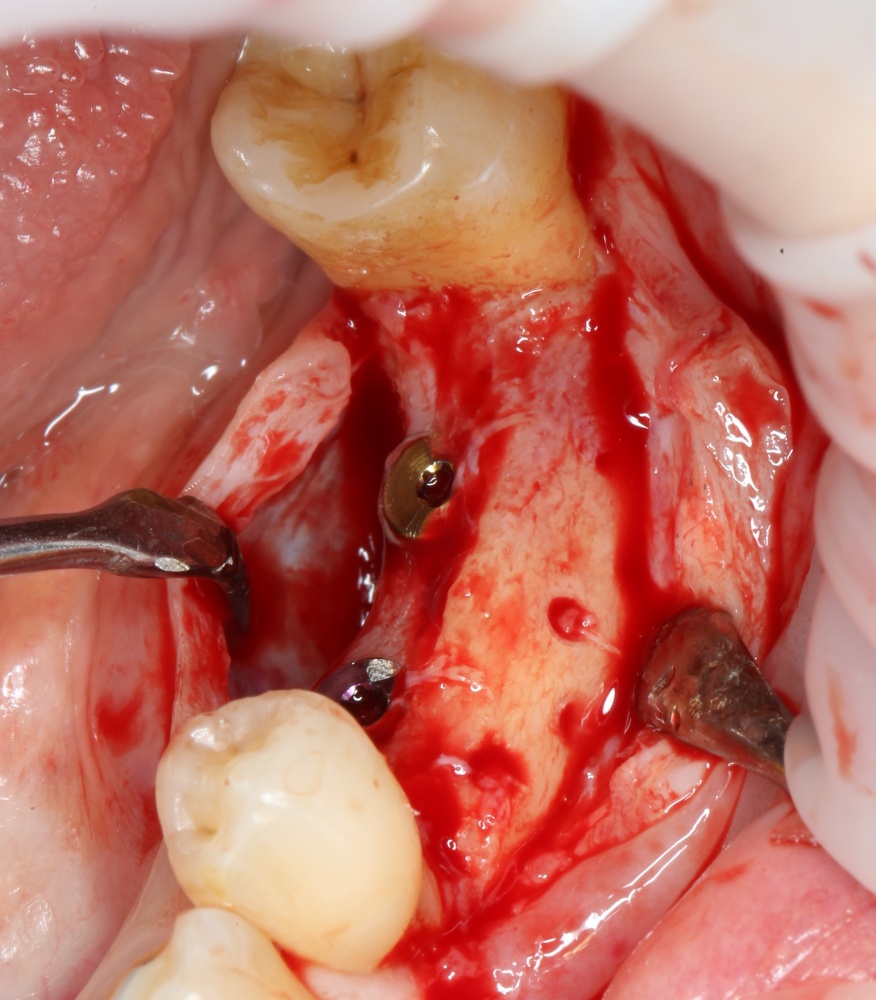

Скелетирование альвеолярного гребня. В том числе, участка для забора аутокостного трансплантата:

A09A5445 (2) A09A5446 (2)

Не нужно скелетировать весь альвеолярный гребень целиком. Мы делаем это только в тех участках, которые необходимы для работы в настоящий момент. Потом, при необходимости, можно будет расшириться.

Следующим этапом происходит формирование и забор аутокостного фрагмента для пересадки:

A09A5447 (2) A09A5448 (2)